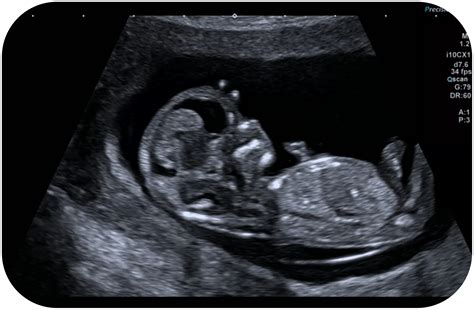

Il Bi-test è un esame di diagnostica prenatale, che si effettua tra la undicesima e la tredicesima settimana di gravidanza. Non si tratta di un test diagnostico definitivo, bensì di un’indagine di screening probabilistico. La sua forza risiede nell'integrazione di dati biochimici ed ecografici. Consiste nel dosaggio delle proteine Free Beta-HCG e PAPP-A, che viene confrontato con le informazioni provenienti dalla translucenza nucale (ecografia ostetrica).

La translucenza nucale (NT) è una valutazione ecografica che misura lo spessore della falda di liquido situata nella regione nucale del feto. Questo parametro, combinato con i livelli plasmatici materni, permette di ottenere una stima statistica molto raffinata. Il Bi-test è impiegato per determinare il rischio della presenza di cromosomopatie nel feto, con particolare riferimento alla T21 (Sindrome di Down), alla T18 (Sindrome di Edwards) e alla T13 (Sindrome di Patau). La precisione di tale esame è strettamente legata alla qualità dell'attrezzatura utilizzata e all'esperienza del medico ecografista, elementi che a Catania trovano riscontro in centri specializzati di alto profilo.

Il processo che porta all'elaborazione dell'indice di rischio è un esempio di sinergia tra biologia molecolare e imaging medico. Dal confronto tra i risultati delle analisi del sangue, della translucenza nucale e altre variabili, come l’età materna, si ottiene un indice di rischio. L'età della madre rappresenta un fattore epidemiologico fondamentale, ma non è l'unico; l'integrazione con i marker biochimici permette di personalizzare il rischio per la specifica gravidanza in corso.